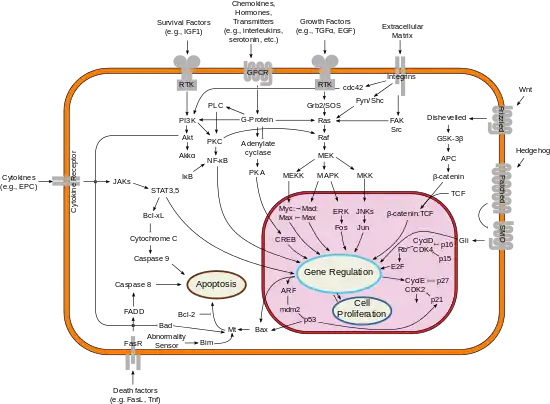

Pathophysiology

Breast cancer, like other cancers, occurs because of an interaction between an environmental (external) factor and a genetically susceptible host. Normal cells divide as many times as needed and stop. They attach to other cells and stay in place in tissues. Cells become cancerous when they lose their ability to stop dividing, to attach to other cells, to stay where they belong, and to die at the proper time.

Normal cells will self-destruct (programmed cell death) when they are no longer needed. Until then, cells are protected from programmed death by several protein clusters and pathways. One of the protective pathways is the PI3K/AKT pathway; another is the RAS/MEK/ERK pathway. Sometimes the genes along these protective pathways are mutated in a way that turns them permanently "on", rendering the cell incapable of self-destructing when it is no longer needed. This is one of the steps that causes cancer in combination with other mutations. Normally, the PTEN protein turns off the PI3K/AKT pathway when the cell is ready for programmed cell death. In some breast cancers, the gene for the PTEN protein is mutated, so the PI3K/AKT pathway is stuck in the "on" position, and the cancer cell does not self-destruct.[98]

Mutations that can lead to breast cancer have been experimentally linked to estrogen exposure.[99] Additionally, G-protein coupled estrogen receptors have been associated with various cancers of the female reproductive system including breast cancer.[100]

Abnormal growth factor signaling in the interaction between stromal cells and epithelial cells can facilitate malignant cell growth.[101][102] In breast adipose tissue, overexpression of leptin leads to increased cell proliferation and cancer.[103]